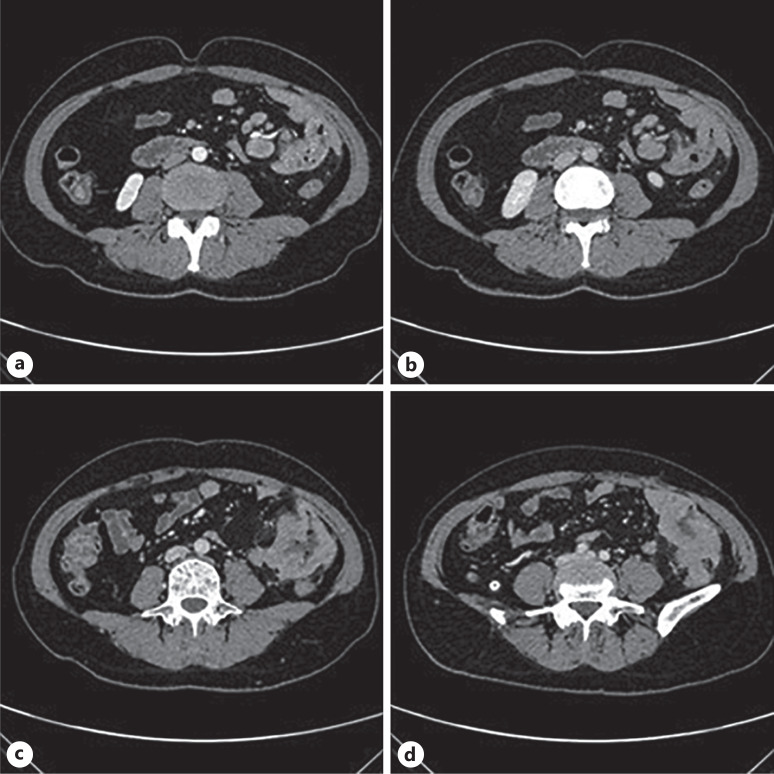

Case presentation: We report the case of a 47-year-old woman who presented with a 2-month history of left lower abdominal pain and discomfort. Imaging studies, including enhanced abdominal CT and PET-CT, revealed a suspicious mass in the jejunum. Comprehensive diagnostic evaluations excluded metastatic origins, and a diagnosis of primary small intestinal SCC was confirmed by histopathology and immunohistochemistry. The patient underwent radical surgical resection, which revealed a poorly differentiated SCC invading the serosa and regional lymph nodes. Postoperative management included infection prevention and fluid rehydration, with recommendations for adjuvant chemotherapy and immunotherapy based on multidisciplinary consultation. Despite the advanced disease stage, the patient recovered well post-surgery and is undergoing regular follow-up.